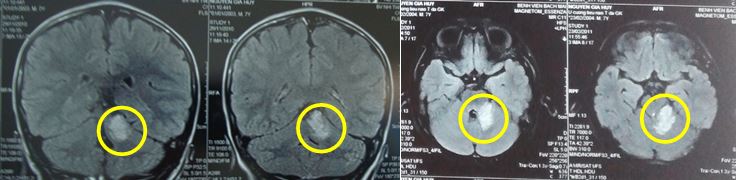

Kết quả chụp cộng hưởng từ sọ não cho thấy:

Hình ảnh cộng hưởng sọ não từ trước điều trị: Kích thước khối u: 3,2 x 2,8cm

Hình ảnh cộng hưởng từ sọ não sau xạ phẫu 3 năm: Khối u đáp ứng tốt, chỉ còn hình ảnh tăng tín hiệu nhẹ trên T2, không ngấm thuốc đối quang từ, kích thước 0,8 x1cm